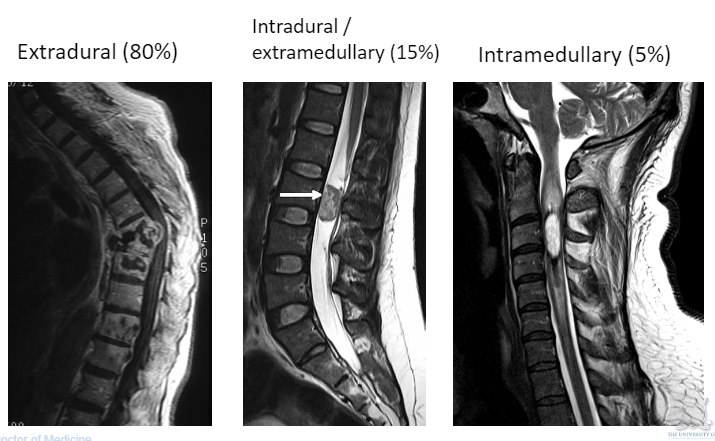

Recognise the appearance of extradural, intradural/extramedullary and intramedullary lesions which may compress the spinal cord and cauda equina. Which is the most common?

Give 3 examples of extradural causes of spinal cord and cauda equina compression

Give 3 examples of intradural/extramedullary causes of spinal cord and cauda equina compression

Give 2 examples of intramedullary causes of spinal cord and cauda equina compression